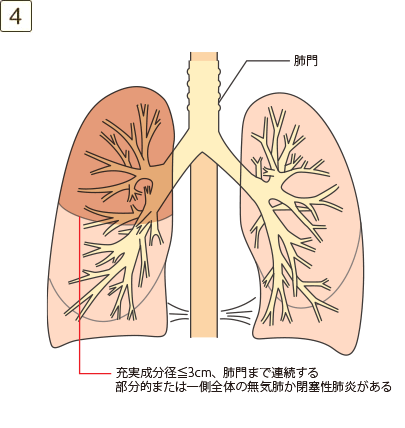

充実成分径>3cmでかつ≦5cm、または充実成分径≦3cmでも以下のいずれかであるもの

- ・肺門まで連続する部分的または一側全体の無気肺か閉塞性肺炎がある